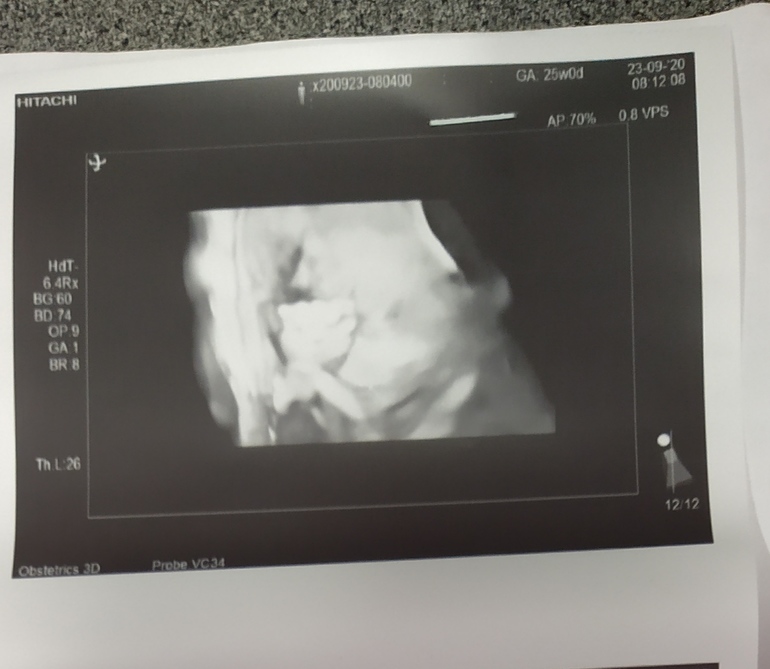

И наш цветочек, Сомнений больше нет, что девочка у нас 🎀